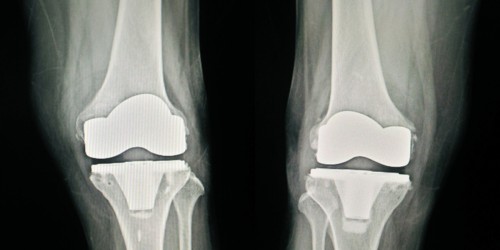

I am writing on my behalf of my Dad (67 years old) who has had a rough ride starting from July 2022 when he underwent right TKR.

The knee was never quite right and after it being confirmed he was suffering from a bad infection at the start of 2023, he underwent a two stage TKR revision involving complex plastic surgery.